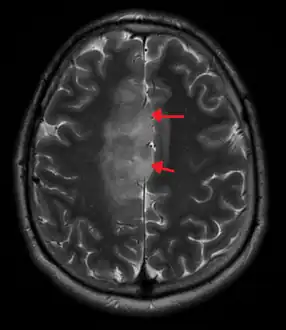

A oligoastrocytoma on CT

An X-ray computed tomography (CT) or magnetic resonance imaging (MRI) scan is necessary to characterize the anatomy of this tumor as to size, location, and its heter/homogeneity. However, final diagnosis of this tumor, like most tumors, relies on histopathologic examination (biopsy examination).[3]